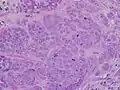

-

High-grade invasive ductal carcinoma, with minimal tubule formation, marked pleomorphism, and prominent mitoses, 40x field

High-grade invasive ductal carcinoma, with minimal tubule formation, marked pleomorphism, and prominent mitoses, 40x field -

Breast cancers are classified by several grading systems, each of which assesses a tumor characteristic that impacts a person's prognosis. First, a tumor is classified by the tissue it arises from, or the appearance of the tumor tissue under a microscope. Most breast cancers (85%) are ductal carcinoma – derived from the lining of the mammary ducts. 10% are lobular carcinoma – derived from the mammary lobes – or mixed ductal/lobular carcinoma.[45] Rarer types include mucinous carcinoma (around 2.5% of cases; surrounded by mucin), tubular carcinoma (1.5%; full of small tubes of epithelial cells), medullary carcinoma (1%; resembling "medullary" or middle-layer tissue), and papillary carcinoma (1%; covered in finger-like growths).[45] Oftentimes a biopsy reveals cells that are cancerous but have not yet spread beyond their original location. This condition, called carcinoma in situ, is often considered "precancerous" rather than a dangerous cancer itself.[46] Those with ductal carcinoma in situ (in the mammary ducts) are at increased risk for developing true invasive breast cancer – around a third develop breast cancer within five years.[46] Lobular carcinoma in situ (in the mammary lobes) rarely causes a noticeable lump, and is often found incidentally during a biopsy for another reason. It is commonly spread throughout both breasts. Those with lobular carcinoma in situ also have an increased risk of developing breast cancer – around 1% develop breast cancer each year. However, their risk of dying of breast cancer is no higher than the rest of the population.[46]

Invasive tumor tissue is assigned a grade based on how distinct it appears from healthy breast.[47] Breast tumors are graded on three features: the proportion of cancer cells that form tubules, the appearance of the cell nucleus, and how many cells are actively replicating.[48] Each feature is scored on a three-point scale, with a higher score indicating less healthy looking tissue. A grade is assigned based on the sum of the three scores. Combined scores of 3, 4, or 5 represent grade 1, a slower-growing cancer. Scores of 6 or 7 represent grade 2. Scores of 8 or 9 represent grade 3, a faster-growing, more aggressive cancer.[47]